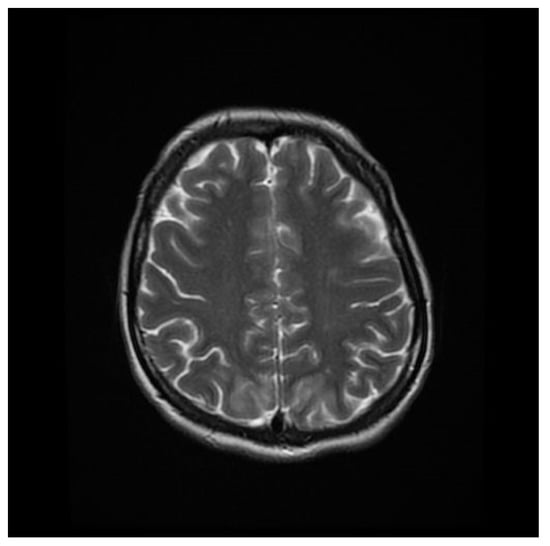

Computed tomography (CT) angiography of the head and CT with contrast were performed and excluded aneurysm, arteriovenous malformation (AVM), dural sinus thrombosis, and tumor. Due to the lack of deviations in the previous tests, an MRI of the head with contrast was performed, in which small areas and hyperintense bands in the T2-weighted image (T2-WI) and Fluid Attenuated Inversion Recovery (FLAIR) were visualized on both sides in the parieto-occipital areas without either diffusion restrictions or contrast enhancement, a typical manifestation of PRES [4], as shown in Figure 1, Figure 2, Figure 3 and Figure 4.

Figure 3. T2-WI MRI sequence of the brain in transverse plane.

Brainsci 12 00915 g003

Figure 4. T2-WI MRI sequence of the brain in horizontal plane.